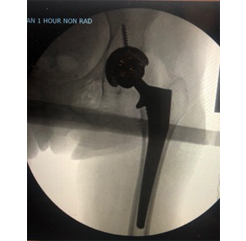

40 something year old s/p anterior total hip performed by outside surgeon 6 weeks ago involved in motor vehicle accident with resultant femur fracture around her total hip and de-stablization of the femoral prosthesis.

Hip revision performed through ANTERIOR APPROACH with cables placed to reduce fracture and placement of revision femoral prosthesis.

Before

After